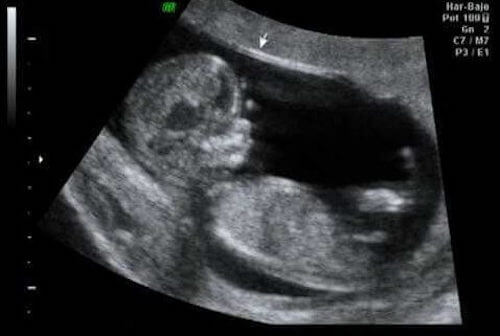

Gebeliğin 12. haftasında ultrason

12. hafta, ilk trimesterin dönüm noktası olarak, ilk ultrason için ideal bir zaman olabilir. Böylece, organların doğru şekilde gelişip gelişmediğini doğrulayabilirsiniz. Ayrıca bebeğin boyutunu, ağırlığını ve ensesindeki yarı saydamlığı kontrol edebiliriz.

Bu önemli bir zamandır; uzmanlar bu noktada kusurların %60 ila %70’ını tespit edebilir.

“Öte yandan, fetüsün ensesi ölçülür. Bu, ilk trimesterdeki kontrolün bir parçasıdır, aneuploid olarak bilinen kromozom sayısında olası bir anomali riskini – özellikle Trizomi 21 ya da Down sendromu – algılamamıza izin verir.” Bunu belirlemek, veriler ve aşağıdaki benzer değerlendirmeler sayesinde mümkündür:

- Ense saydamlık değerleri

“Fetüs kusurlarının %60 ve %70’i ilk ultrasonda tespit edilebilir”

Fetüsün ilk aktivitelerini fark etmenin yanı sıra heyecan verici bir kısım da, doğum için son tarihin tahminidir. Herhangi bir durumda, bu tarih sadece % 5 oranında doğrudur.